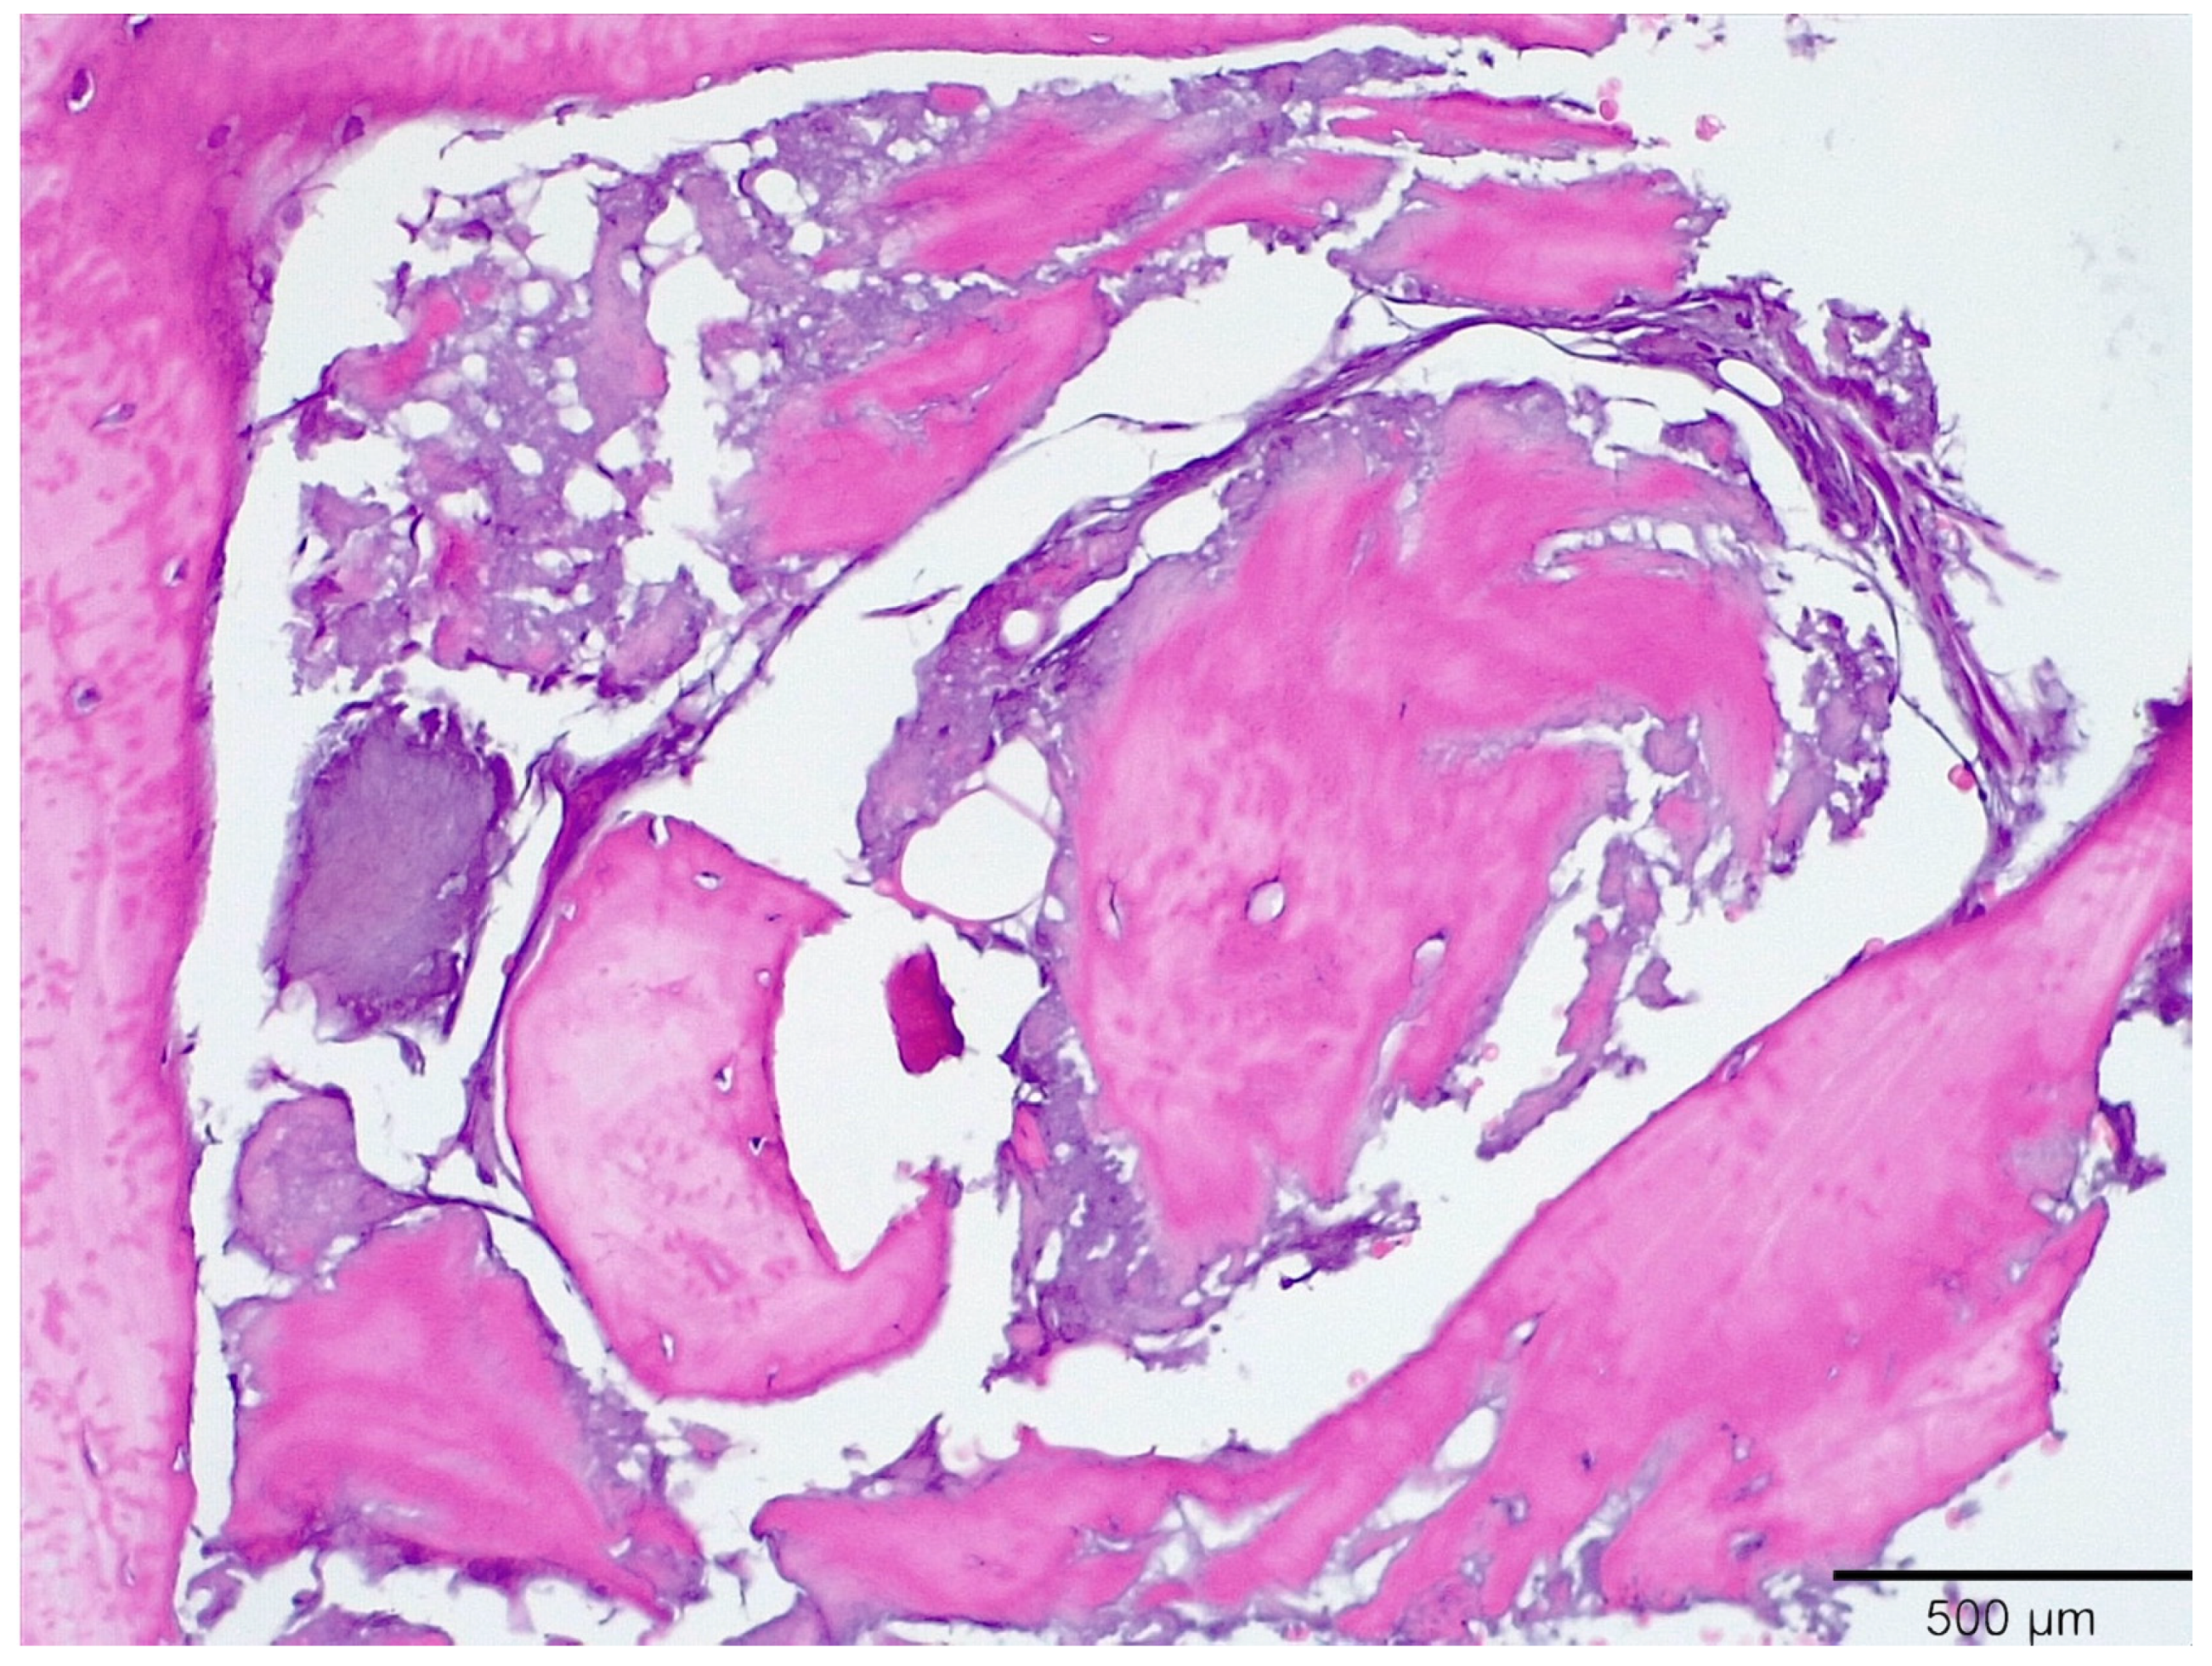

3.1. Histological Analysis Showed Signs of New Bone Formation at 60 Days

3.2. Histologic Data Obtained after Samples Analysis at 24 Months of Evaluation

| New bone | 16.3 ± 1.98 | 41.1 ± 0.76 | 54.5 ± 0.24 | 59.4 ± 1.23 * |

| Residual Graft | 37.1 ± 0.34 | 30.0 ± 0.45 | 21.3 ± 0.88 | 15.6 ± 086 |

| Connective tissue | 46.6 ± 0.11 | 29.9 ± 0.56 | 24.2 ± 0.32 | 25.0 ± 0.44 |